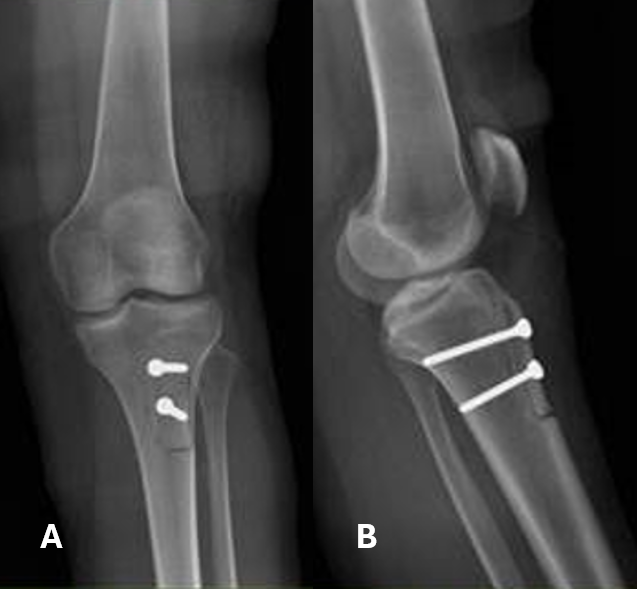

During the arthroscopic portion of the surgery in May 2023, a grade 1 chondral lesion on the lateral patellar facet was identified according to the Outerbridge classification, and lateral retinacular release was performed. During the second part, the tibial tuberosity (TT) was medialized by 1 cm and secured with two 4.5 mm lag screws, achieving a TT-TG distance up to 10 mm in the final measurement (Fig. 1).

Figure 1: (a) Anteroposterior and (b) lateral view of the left tibia immediately after tibial tuberosity osteotomy fixed with 4.5 screws.